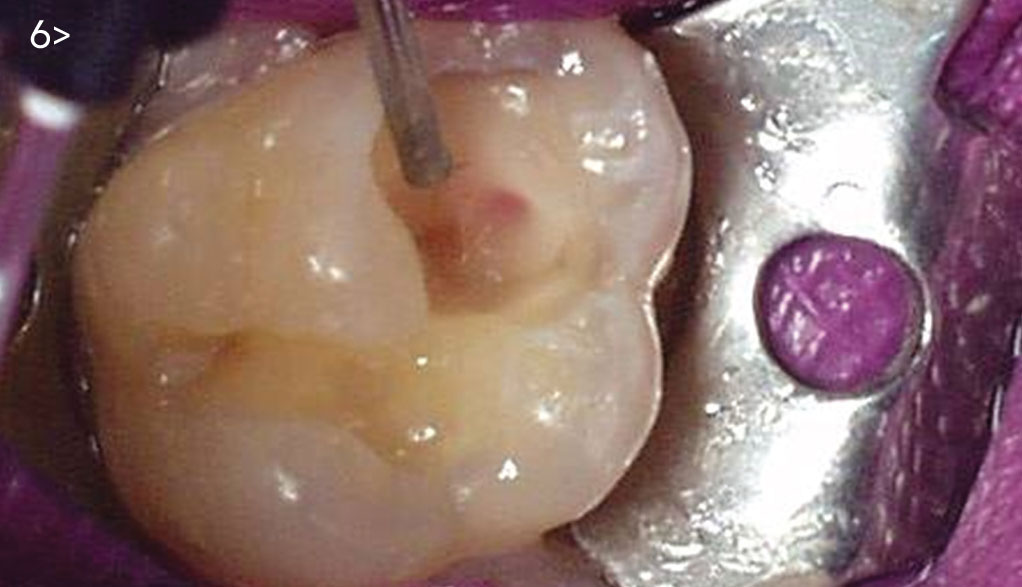

- Fig. 1: Carious pulp exposure appears greenish yellow and possibly purulent.

Endodontic root-canal therapy is indicated.